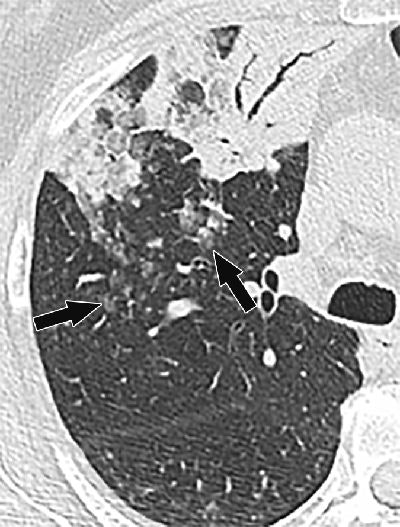

CT image shows primary lung invasive mucinous adenocarcinoma in right upper lobe presenting as air-space consolidation with air bronchograms in 68-year-old man. Ill-defined centrilobular nodules (arrows) with ground-glass attenuation are present posterior to lesion."Growing evidence in the literature suggests that aerogenous spread of lung adenocarcinoma is an underrecognized form of tumor progression, having distinct pathologic and imaging findings and potentially major management implications," the authors concluded. "The presence of persistent or growing centrilobular nodules on CT images should be considered suspicious for aerogenous spread in patients with primary lung adenocarcinoma, particularly those with invasive mucinous, papillary, and micropapillary subtypes."